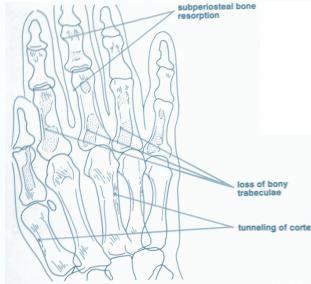

- Sub-periosteal bone resorption (most specific finding)

- Sub-periosteal resorption: middle phalanges, tibial shaft

- In hand, sub-periosteal bone resorption .This change usually happen in the middle phalanges, radial aspect in the 2nd or 3rd finger.

- Terminal tuft erosion.

Sub-periosteal bone resorption

- Most useful sign

- Virtually Diagnostic

- Location

Subperiosteal bone resorption (straight arrow), resorption of the tip of the terminal phalanx and the altered bone architecture. Arterial calcification is also present (curved arrow).